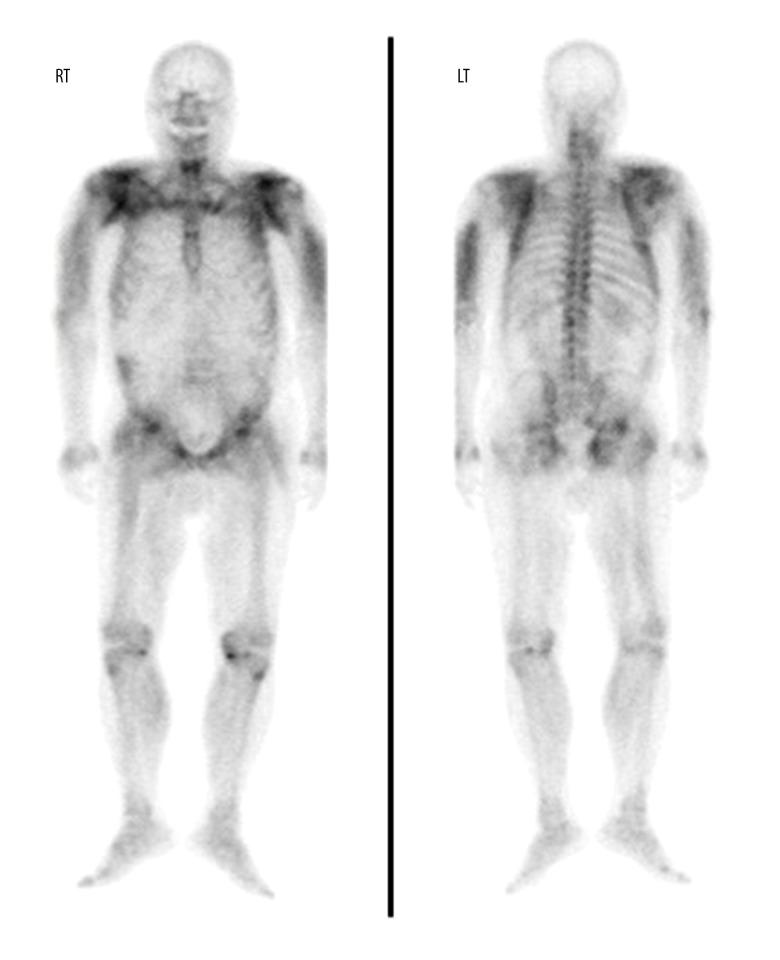

2

The clinical significance of technetium-99m methylene diphosphonate bone scintigraphy findings in patients with rhabdomyolysis.99m锝亚甲基二膦酸盐骨闪烁显像结果在横纹肌溶解症患者中的临床意义。

Nucl Med Commun. 2017 Oct;38(10):820-825. doi: 10.1097/MNM.0000000000000709.